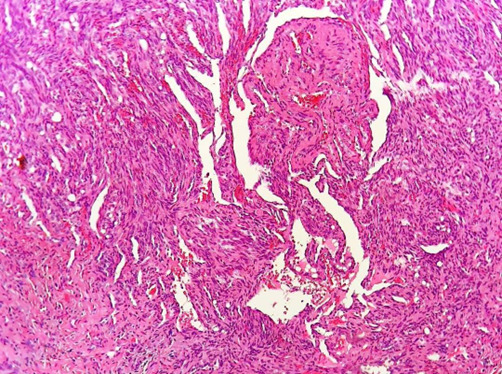

梭形细胞血管瘤(SCH),以前称为“梭形细胞血管内皮瘤”,是一种罕见的良性血管瘤的组织学变异,其特征是存在两个对比区,第一个区表现为巨大的扩张的海绵状空间,裂缝状血管空间可显示清晰的内皮空泡,类似脂肪细胞。SCH常被认为是假肉瘤;由于它与卡波西肉瘤相似,对口腔病理学家的诊断提出了挑战。迄今为止,头颈部共报告了13例SCH,而口腔内仅报告了6例。我们报告一例罕见的位于硬腭的SCH,其组织病理检查与卡波西氏肉瘤相似。EGR、cd31、HHV - 8等标志物的表达是SCH的最终诊断依据。据我们所知,EGR和HHV - 8标志物从未用于口腔内SCH;因此,本报告强调使用免疫组织化学诊断SCH。

Spindle cell hemangioma (SCH), formerly called "spindle cell hemangioendothelioma", is a rare benign histological variant of hemangioma characterized by the presence of two contrast zones, the first zone exhibits large dilated cavernous space with slit-like vascular spaces may show clear endothelial vacuoles resembling fat cells. SCH is often considered as pseudosarcomatous entity; it imposes a diagnostic challenge for oral pathologists due to its resemblance with Kaposi sarcoma. A total of 13 cases of SCH have been reported in the head and neck region to date and only 6 cases have been reported inside the oral cavity. We present a rare case of SCH located on the hard palate, which imitated Kaposi's sarcoma on histopathological examination. The expressions of various markers including EGR, CD 31, and HHV 8 yielded the final diagnosis of SCH. The markers EGR and HHV 8 have never been used in intraoral SCH before to the best of our knowledge; hence, the present report highlights the use of immunohistochemistry for the diagnosis of SCH.